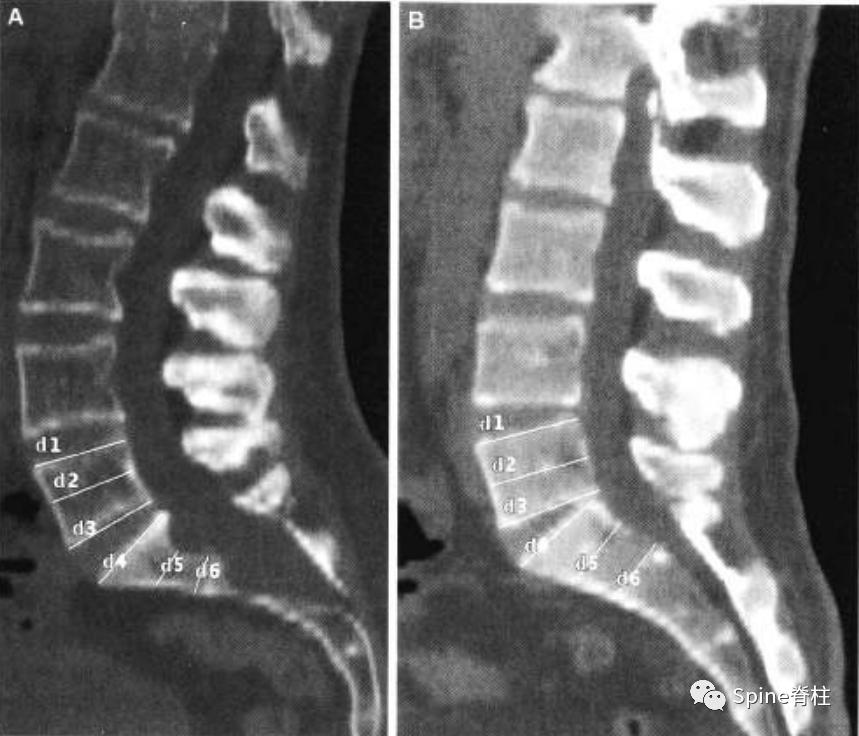

扇形缺损 (scalloping) 的测量。图a为马凡综合征伴硬膜扩张患者的CT正中矢状位重建。扇形缺损定义为椎体上下终板处宽度的平均值减去椎体中央处的宽度。对于这位患者来说,L5的扇形缺损值 (scalloping value) =[(d1+d3)/2]-d2=2.3mm;S1扇形缺损值=[(d4+d6)/2]-d5=4.2mm。图b是马凡综合征不伴硬膜扩张患者的CT正中矢状位重建。L5的扇形缺损值为1.6mm,S1扇形缺损值为0.4mm。

一位马凡综合征伴硬膜扩张患者的CT图像。a为正中矢状位重建,可见S2的椎管宽度大于L4。S1扇形缺损值为4.2mm。b为L5水平的横断面提示一个神经根袖的直接为6.6mm。因此,这个患者满足一个主要标准和两个次要标准。